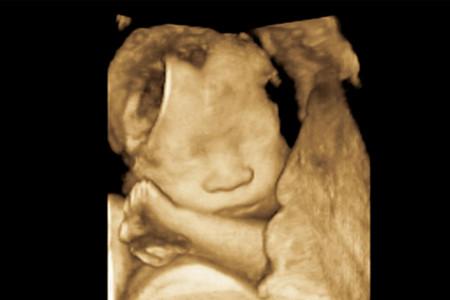

實時三維多普勒超聲(四維)

—— 會動的B超

四維比三維其實就是多了時間這一個維度,看見的寶寶是動態(tài)的,吃手啊,打嗝啊,伸懶腰啊,這些動作都可以看見。

所以也叫實時三維B超。

四維以外的B超,醫(yī)生看屏幕上的內(nèi)容都是一張張的截圖,所以看起來是不連貫的,四維看胎動是非常連貫的。

也就是說如果拍照三維就可以,如果需要視頻四維才可以,三維和四維的機(jī)器一般都是一個,同一個機(jī)器上探頭更換一下,屏幕切換一下就可以實現(xiàn)三維到四維的轉(zhuǎn)換。

所以如果你是想給寶寶錄下一段視頻,就需要做四維,如果只是為了排畸,三維結(jié)合二維已經(jīng)很完美了,二維排畸也是足夠的。